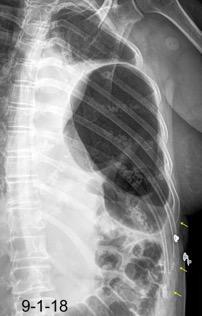

Accidente de tráfico

Rx: Niveles hidroaéreos en hemitórax izquierdo Desviación mediastínica Ausencia de intestino en abdomen. Configuración en reloj de arena del intestino herniado “Tubo nasogástrico”

Furak J et al. Diaphragm and transdiaphragmatic injuries. J Thorac Dis 2019

Recibe una puñalada en costado izquierdo

La laceración tiende a ocurrir en la unión

músculotendinosa . (64-90% en el lado izquierdo)